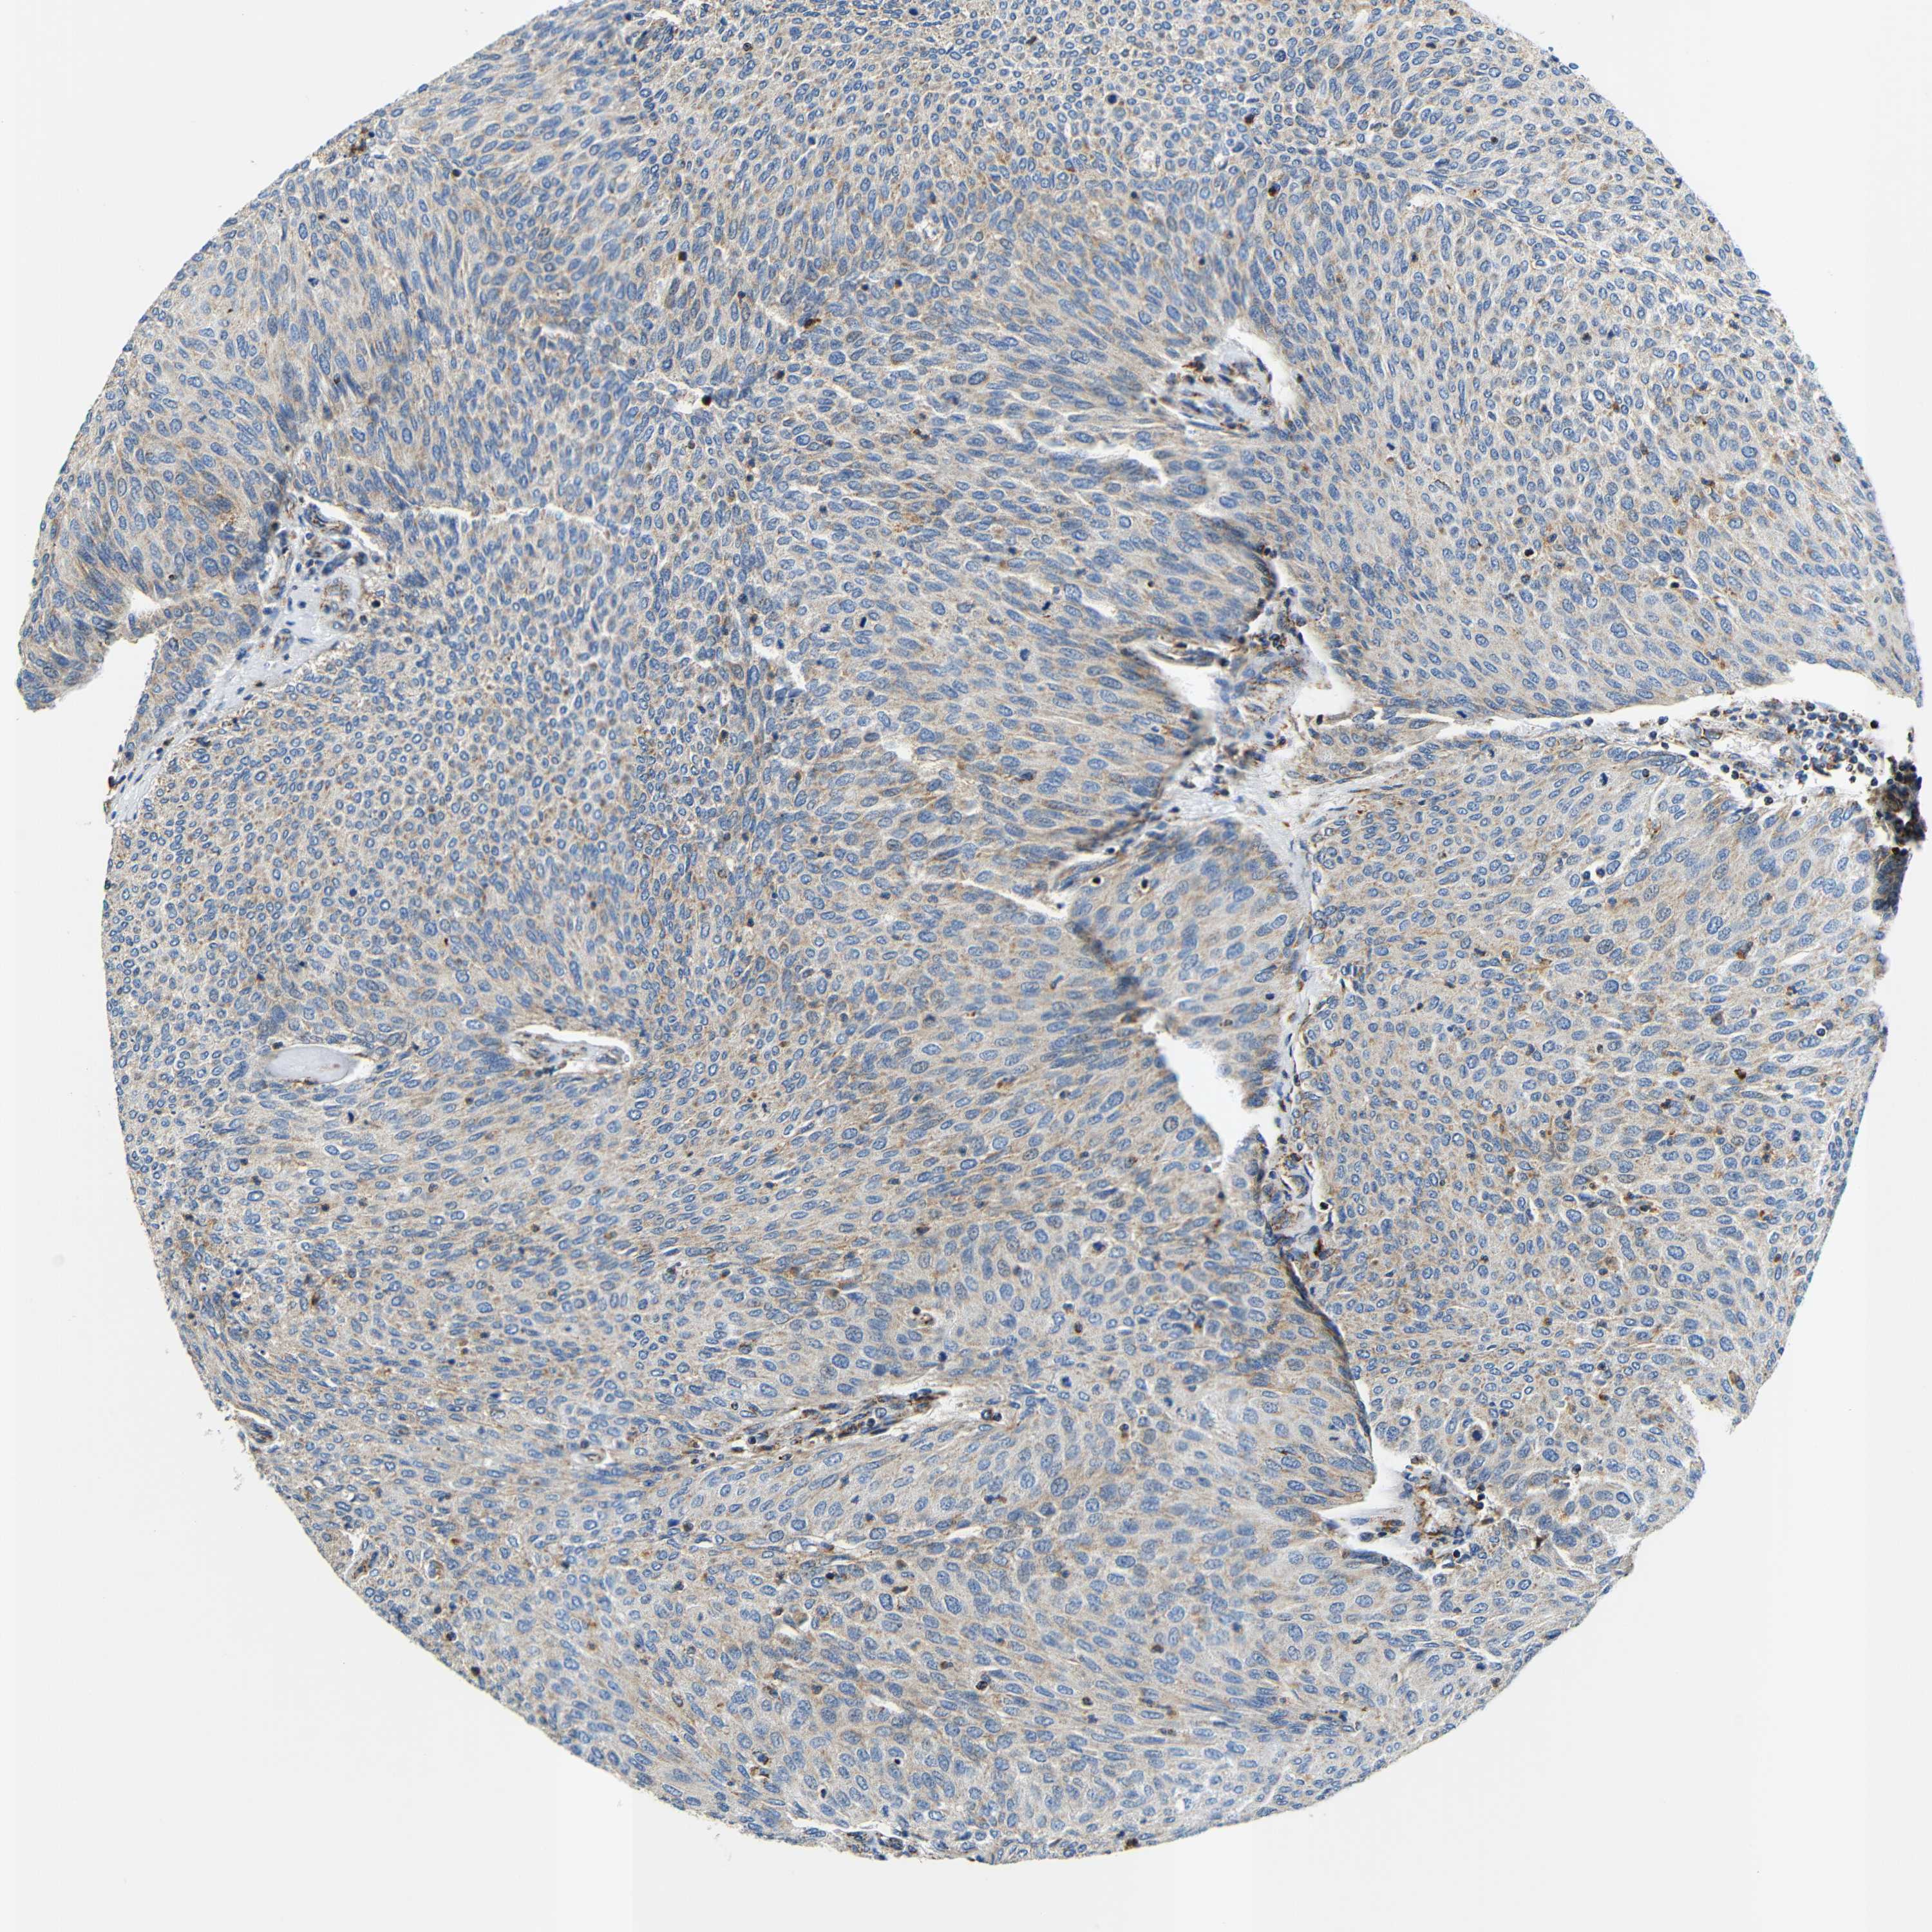

UROTHELIAL CANCER - Protein expressioni

A mouse-over function shows sample information and annotation data. Click on an image to view it in a full screen mode. Samples can be filtered based on level of antibody staining by selecting one or several of the following categories: high, medium, low and not detected. The assay and annotation is described here.

Note that samples used for immunohistochemistry by the Human Protein Atlas do not correspond to samples in the TCGA dataset.

Antibody stainingi

Antibody staining in the annotated cell types in the current human tissue is reported as not detected, low, medium, or high, based on conventional immunohistochemistry profiling in selected tissues. This score is based on the combination of the staining intensity and fraction of stained cells.

Each image is clickable and will lead to virtual microscopy that enables deeper exploration of all samples and also displays staining intensity scores, fraction scores and subcellular localization as well as patient and tissue information for each sample.

Antibody HPA012955

Staining

High

Medium

Low

Not detected

Intensity

Strong

Moderate

Weak

Negative

Quantity

>75%

75%-25%

<25%

None

Location

Nuclear

Cytoplasmic/membranous

Cytoplasmic/membranous,nuclear

Urothelial carcinoma, Low grade

Urothelial carcinoma, High grade